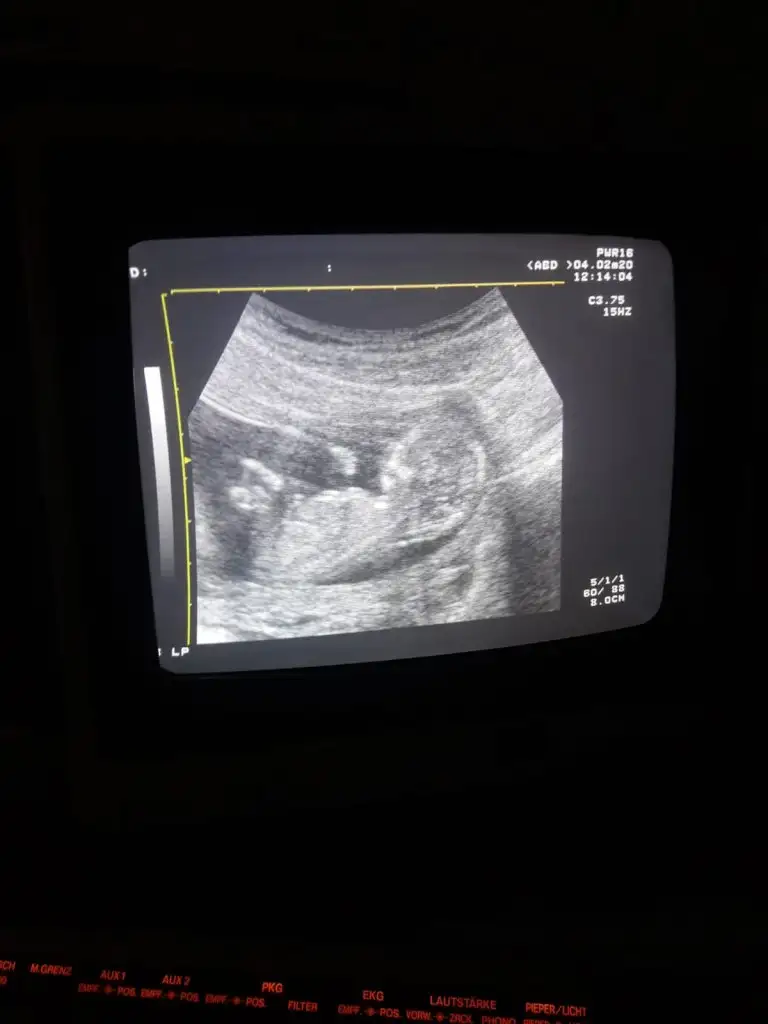

11 haftalikken kiz demistiniz ve Evet 18+4 te doktor kiz bebek dedi ☺Kız gibi diyorum net degil usg başka varmı 12+ hafta usgde paylaşın

Kız gibi tam net degil başka ush paylaşın 12 de olır13+1 sizce ?

Kız gibi gibi kaç haftalık bu usgBu arkası dönük olmazmi![]()

Başka usg varmı çok net değil diklik görünüyor sanki erkek gibi emin olamıyorum12 haftalık acaba cinsiyet tahmininde bulunabilir misiniz

Başka usg varmı çok net değil diklik görünüyor sanki erkek gibi emin olamıyorum

Yaa yukardan arkadaş bana mesaj yazıyorduYani şu gördüğüm nub ise dik görünüyor bacaklar yukarda nubunu değiştirmiyorsa pozisyon erkek gibiEki Görüntüle 2584968